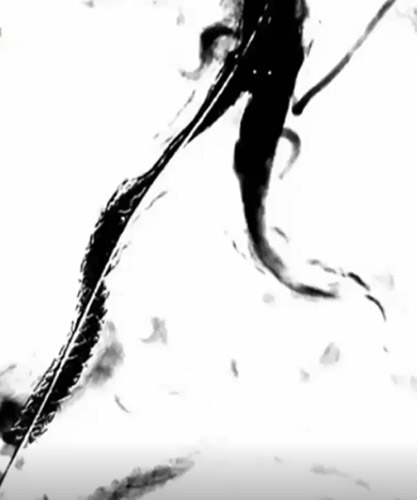

レトログレードから6gワイヤー(0,014“)で病変を通過させ、AnteOwl WRで確認したところ、石灰化部で偽腔を通過していることを確認した(図3)(図4)。

レトログレードからAnteOwl WRのTipDitection法でintra-plaque内を捉えた。今までのIVUS-GuideではAngio-Viewを都度振って対比していたが、最近は最初にAngioとIVUSのフュージョンを行い一方向に固定した上で、トランスデューサーの位置を変えながらワイヤーの距離やチップの向きを確認し、intra-plaque内を捉える手技に変化しつつある(図5)(図6)。